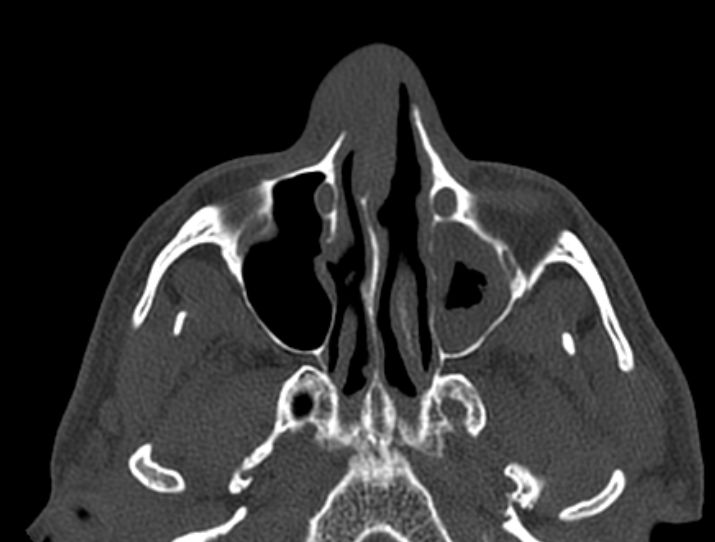

Diagnostik | Tumor

der Nasenhaupthöhle mit Zerstörung des Nasenseptums uns Infiltration der

Nasenhaut.![]() ![]() | ||